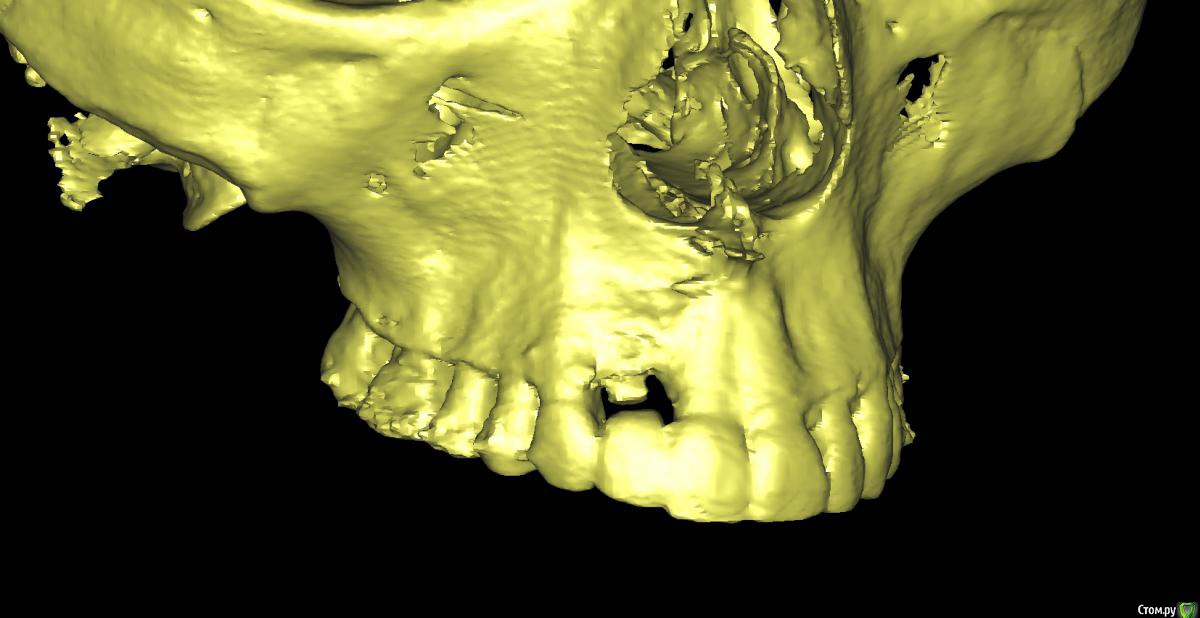

Irouil Опубликовано 1 сентября, 2019 Поделиться Опубликовано 1 сентября, 2019 Тут бы рентген смотреть Ссылка на комментарий

x4ex Опубликовано 1 сентября, 2019 Автор Поделиться Опубликовано 1 сентября, 2019 Тут бы рентген смотреть Ссылка на комментарий

Дмитрий М Опубликовано 3 сентября, 2019 Поделиться Опубликовано 3 сентября, 2019 12 - имплантат.так по снимку 12 - свой зуб! это резорбция у шейки или недозаглубили? Ссылка на комментарий

Dman Опубликовано 4 сентября, 2019 Поделиться Опубликовано 4 сентября, 2019 так по снимку 12 - свой зуб! 358.jpg это резорбция у шейки или недозаглубили? по всем снимкам 12- имплант, вы точно врач? опишите пожалуйста, каким именно? ну видно же, что на примерке ишемия, значит абатмент выталкивает мягкие ткани вестибулярно и коронально. Если делать пластику то трансплантат будет находиться и расти в том же направлении. Значит нужно сделать более вогнутый абатмент с переходом в коронку намного ниже, там, куда мы хотим сместить зенит. а для чего глушить? чтобы получить больше мягких тканей, потом сместить их вестибулярно, и получить необходимую высоту. Также будет возможность провести на раскрытии еще пластику и добавить ещею 1 Ссылка на комментарий